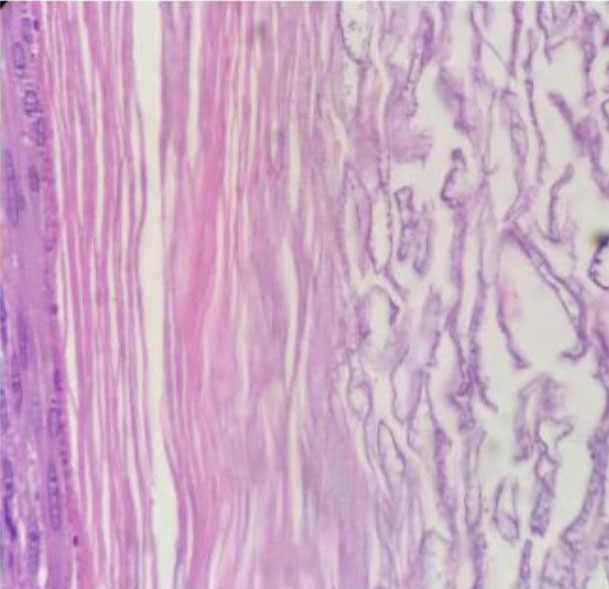

Gross pathological assessment revealed a unilocular cyst containing yellow creamy material, with no skin adnexal elements. Histopathological analysis revealed a thin-walled cyst lined by stratified squamous epithelium with an attenuated granular layer, lamellated keratin, and keratinaceous debris. These features are consistent with the diagnosis of an epidermoid cyst (Figure 4).

Figure 4: Histopathology of the surgical specimen—Hematoxylin and eosin staining showing a thin-walled cyst lined by stratified squamous epithelium with an attenuated granular layer, lamellated keratin, and keratinaceous debris.